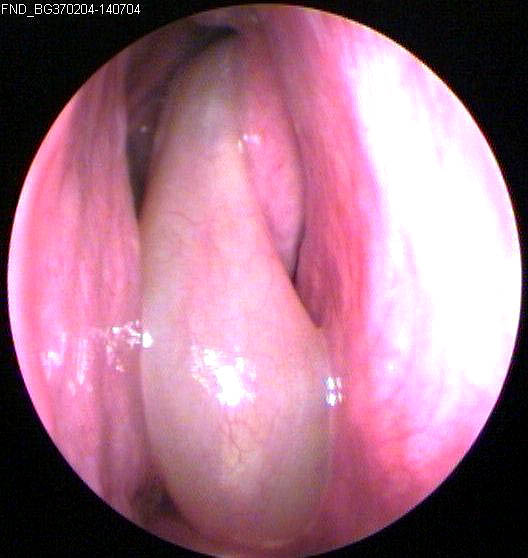

JFC Otopatía izquierda antigua atelectásica con hipoacusia y deformidad del marco